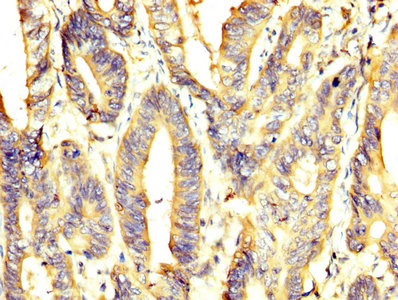

IHC image of CSB-PA018072DA01HU diluted at 1:400 and staining in paraffin-embedded human pancreatic cancer performed on a Leica BondTM system. After dewaxing and hydration, antigen retrieval was mediated by high pressure in a citrate buffer (pH 6.0). Section was blocked with 10% normal goat serum 30min at RT. Then primary antibody (1% BSA) was incubated at 4°C overnight. The primary is detected by a biotinylated secondary antibody and visualized using an HRP conjugated SP system.

IHC image of CSB-PA018072DA01HU diluted at 1:400 and staining in paraffin-embedded human colon cancer performed on a Leica BondTM system. After dewaxing and hydration, antigen retrieval was mediated by high pressure in a citrate buffer (pH 6.0). Section was blocked with 10% normal goat serum 30min at RT. Then primary antibody (1% BSA) was incubated at 4°C overnight. The primary is detected by a biotinylated secondary antibody and visualized using an HRP conjugated SP system.